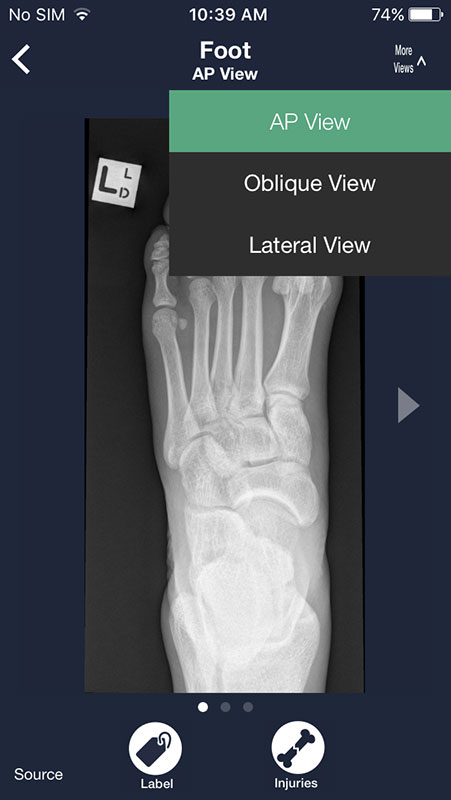

Most radiographs can be viewed from multiple angles. Simply tap on More Views above each image and choose between different views.

For example, you can view shoulder from AP view, apical oblique, or lateral Y, or choose to view chest X-rays from frontal or lateral view, which may be particularly useful to spot some abnormalities that might not be visible from frontal view (for example atelectasis).